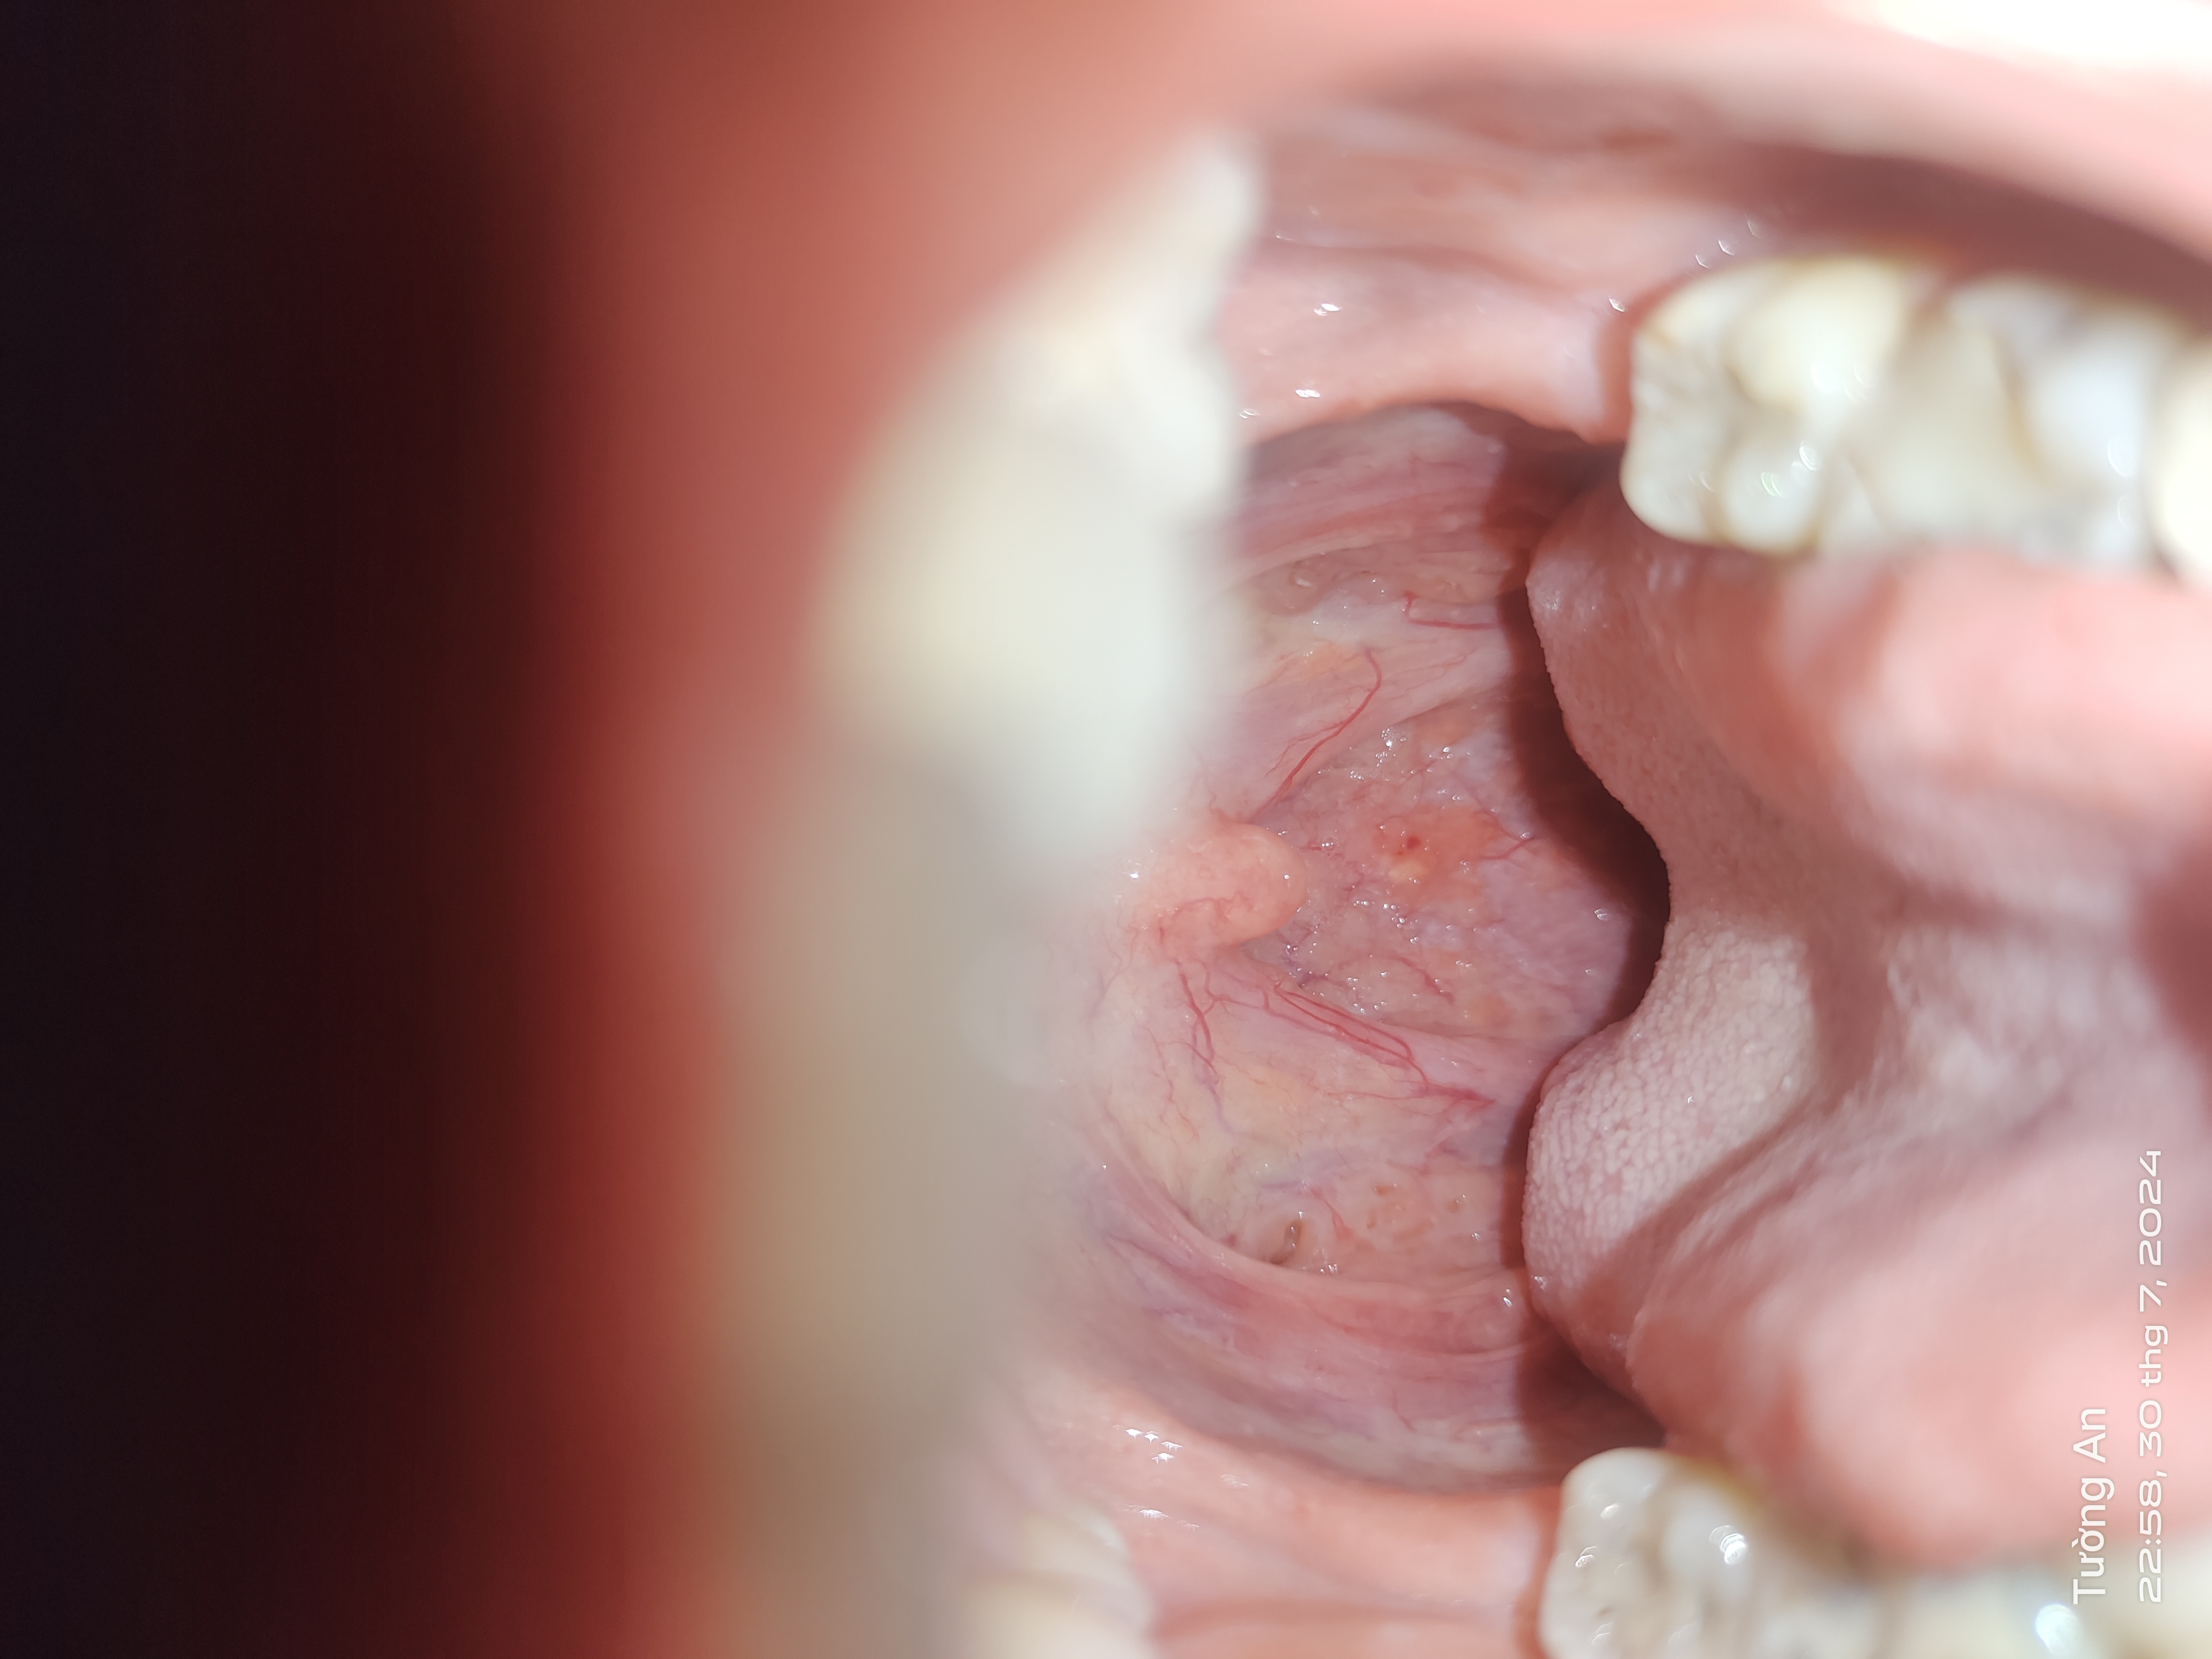

Trong thành cổ họng ngay chổ chấm đỏ có màu vàng (không phải nốt mà nó phẳng với bề mặt da) vậy cổ họng có bất thường không bs

Hình ảnh viêm họng hạt. Các hạt này các hạt lympho lành tính